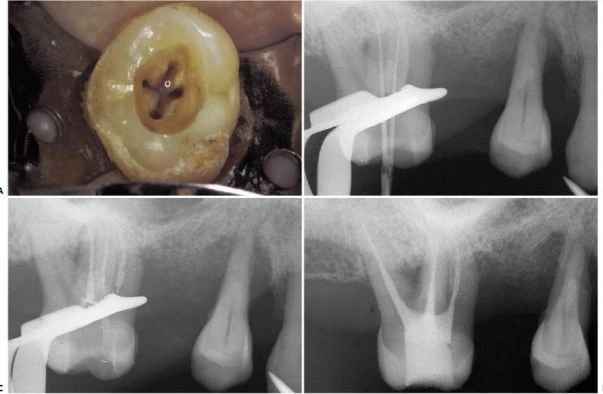

Hình 11.53. A. Sàn tủy của răng #16 với hai miệng ống tủy, một ở trong và một ở ngoài. B. Phim sau điều trị: ống trong dài hơn và một ống ngoài, ống ngoài chia làm hai ống nhỏ hơn ở 1/3 chóp.